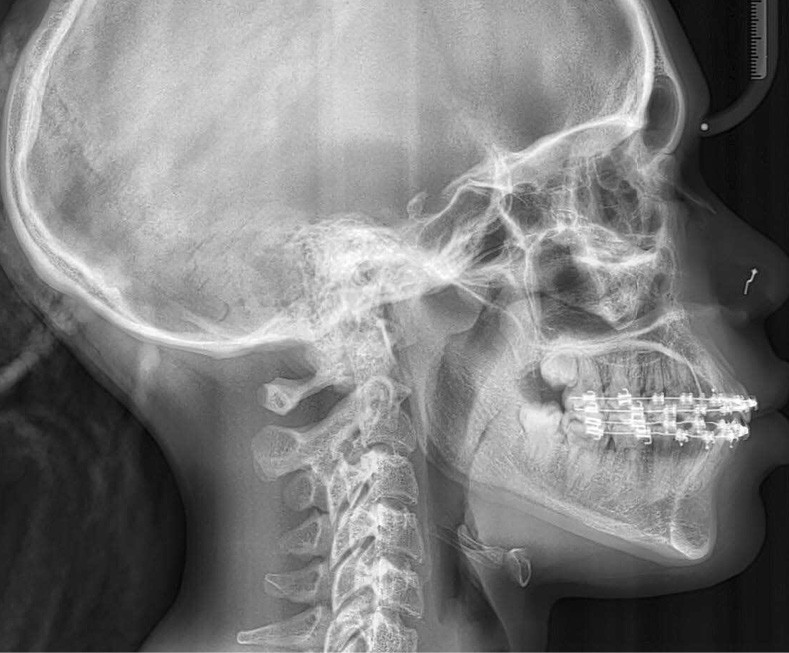

Le profil est plus harmonieux grâce à une diminution de la prochéilie mandibulaire par redressement de l’incisive mandibulaire (fig. 16- 18).

L’auto-transplantation de la 23 sur l’arcade, qui était en position très défavorable, et malgré un apex fermé présente de bons résultats. La radiographie rétro-alvéolaire (fig. 19) montre une intégrité de l’état radiculaire de la dent auto-transplantée. Un suivi régulier reste cependant nécessaire.